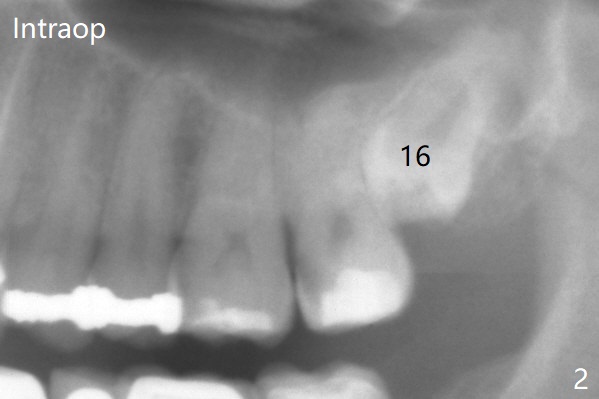

A 37-year-old man complains of food impaction between #14 and 15. Panoramic X-ray shows mesioangular impaction of #16 (Fig.1 ^), which may press #15 root to rotate the tooth so that there is a diastema between #14 and 15. When the impacted tooth is removed, it looks like a microdontia. Intraop X-ray reveals a normal sized 3rd molar in situ (Fig.2: 16). Therefore the microdontia removed is a supernumerary tooth. The tooth #16 is then extracted. The diastema appears to persist 2 years 7 months postop (Fig.3), although gingival swelling and pain reduces. The follow up panoramic X-ray reveals a significant increase in PARL at #20. Return to Professionals Xin Wei, DDS, PhD, MS 1st edition 05/14/2020, last revision 05/16/2020